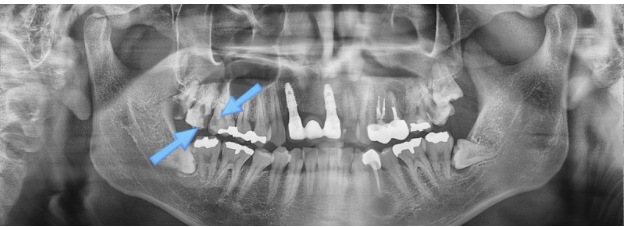

충치가 더 크게 진행된 모습을 확인할 수 있습니다.

이미 심한 통증을 느끼며 내원하신 경우라면, 치료 시기를 놓쳤을 가능성이 높습니다.

가장 뒤쪽의 부러진 사랑니는 발치하였고, 그 앞쪽 화살표로 표시된 두 개의 치아는 신경치료를 진행하게 되었습니다.